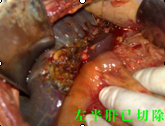

“病情嚴(yán)重,盡快手術(shù)?!薄T主任如是說(shuō)?;颊呷朐汉螅T主任立即召集醫(yī)務(wù)人員進(jìn)行術(shù)前討論,安排醫(yī)生完善各種術(shù)前檢查,制定周密的手術(shù)方案。第二天,他即帶領(lǐng)腫瘤外科經(jīng)驗(yàn)豐富的醫(yī)生為患者實(shí)施了肝門(mén)部膽管癌切除+膽囊切除+左半肝切除,右肝管空腸R-Y吻合術(shù)。在手術(shù)中,由于患者膽囊梗阻部位非常高,腫塊生長(zhǎng)長(zhǎng)度已達(dá)到左右肝總管交界處,手術(shù)過(guò)程中極容易損傷門(mén)靜脈、肝動(dòng)脈及腔靜脈。先切除膽囊,后分離肝、十二指腸韌帶,骨骼化門(mén)靜脈、膽總管、肝動(dòng)脈。見(jiàn)腫塊位于高位膽總管,予以切除左肝總管及肝左葉,行R-Y吻合,整個(gè)手術(shù)僅用了6個(gè)小時(shí),術(shù)中出血極少,手術(shù)過(guò)程非常順利,術(shù)后及時(shí)給予抑酸、抗炎、護(hù)肝補(bǔ)液等對(duì)癥支持治療。經(jīng)過(guò)精心地治療和周到地護(hù)理,現(xiàn)患者恢復(fù)良好。據(jù)統(tǒng)計(jì),此手術(shù)切除機(jī)率不到5%。